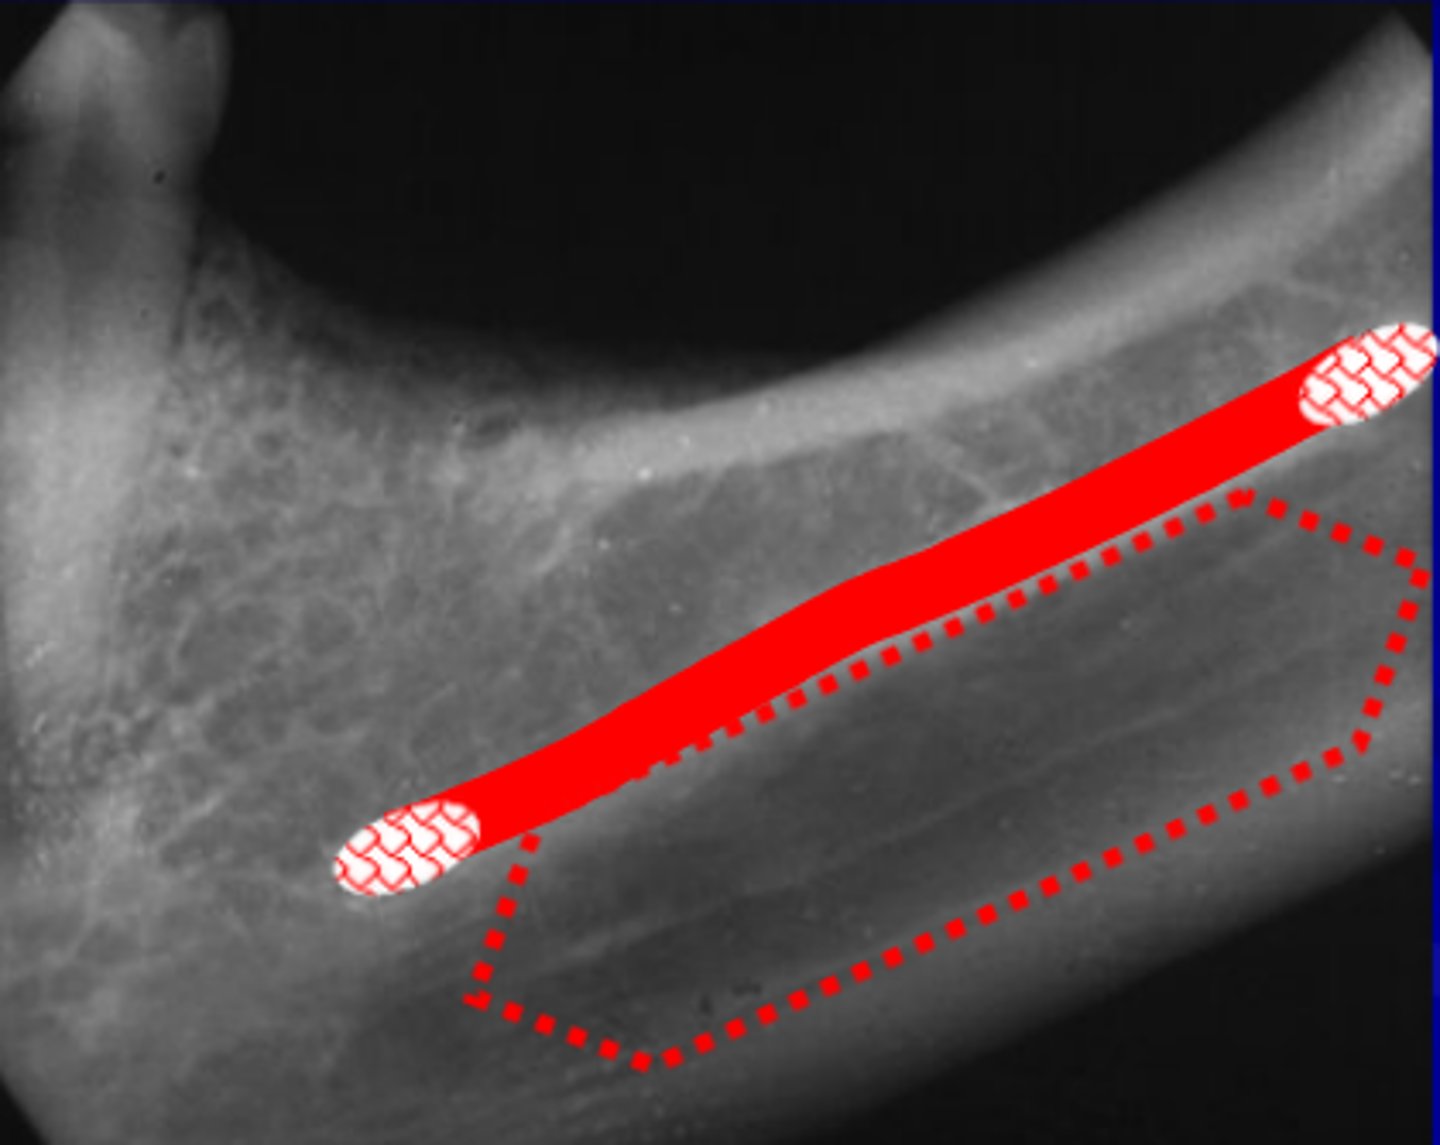

what is this?

what is this radiolucent area in the image?